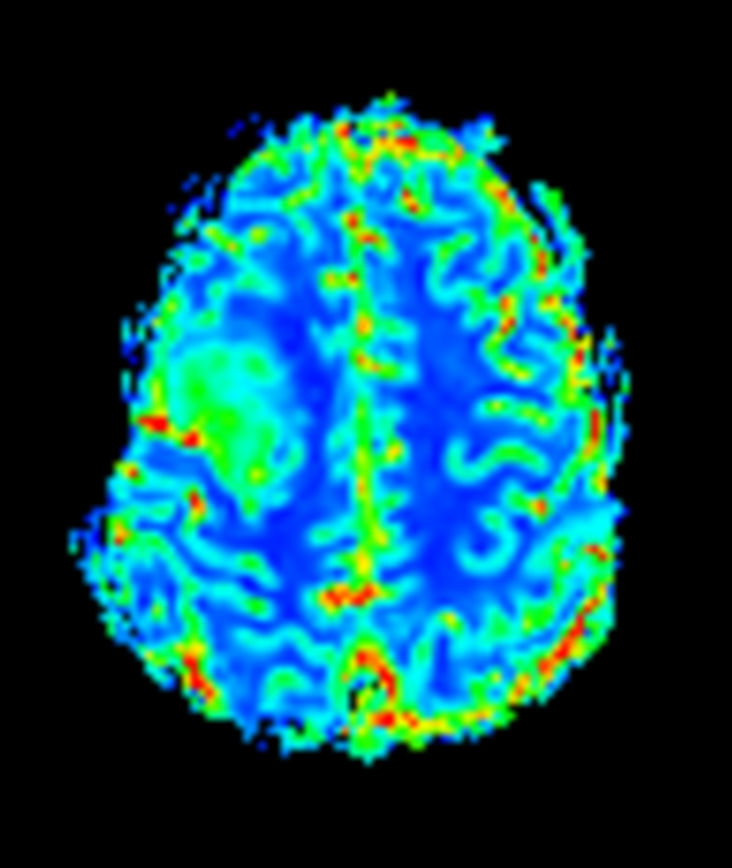

pCASL

Patient with a brain lesion. ExamCard includes MultiVane XD for motion-free imaging in short scan time, Compressed SENSE to shorten exam time, SWIp to enhance contrast for deoxygenated (venous) blood or calcium deposits, a high resolution 3D FLAIR sequence enabling reformats in any plane without loss of resolution, diffusion to achieve high contrast between background and lesions, pCASL to visualize brain perfusion and functional physiology in a non-contrast manner, dynamic multi-slice T2* perfusion for quantitative analysis, and spectroscopy for a non-invasive measurement of biochemical changes in the brain.